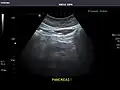

Kidneys: Right and left kidneys measure 11.5 cm and 12 cm in length respectively. No hydronephrosis. Small left lower pole kidney cyst.

Right kidney -